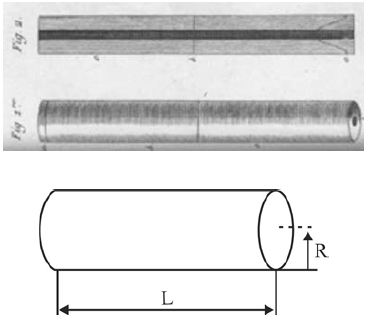

As fibras ópticas são muito utilizadas na medicina para auxiliar nos diagnósticos por imagens. Considere que a fibra esquematizada na figura abaixo tenha comprimento l = 1,0 m, diâmetro d = 0,5 cm, índice de refração nfibra = 1,3 e se encontre no ar, cujo índice de refração considerado seja nar = 1,0. Considere, ainda, que os ângulos θ e α sejam, respectivamente, ângulo de incidência e ângulo de refração da luz com relação à extremidade superior da fibra.

A sensação de um paciente ao ter a campânula de um estetoscópio encostada nele é de que a peça está fria; aos poucos, essa sensação diminui. Considere que essa campânula tenha a forma cilíndrica e seja constituída de uma liga metálica isotrópica com coeficiente de dilatação volumétrico igual 60 × 10-6 °C-1. Considere, ainda, que a peça esteja à temperatura ambiente de 20 °C, tenha diâmetro de 6 cm e espessura de 1 cm, conforme ilustrado na figura abaixo.

Criados em 1816 por René Laennec, os primeiros estetoscópios consistiam em simples tubos de madeira. A função do estetoscópio é permitir a auscultação — escuta dos sons internos do corpo. Com esse aparelho, podem ser examinados os sistemas circulatório, respiratório e até o digestivo, de forma rápida e não invasiva.

As figuras acima ilustram um estetoscópio cujo modelo é o de um tubo de duas extremidades abertas preenchidas com ar. Com base nesses dados e em aspectos relacionados à propagação do som, assinale a opção correta.